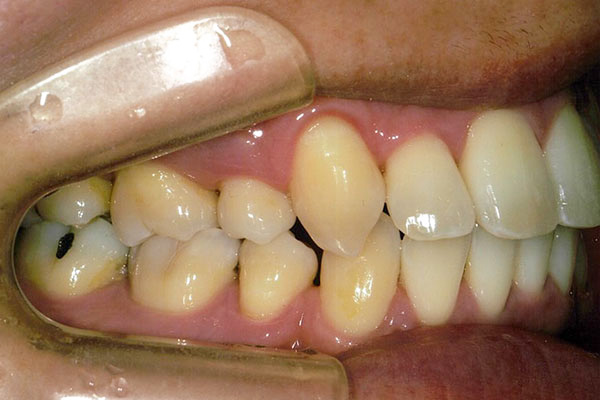

治療前